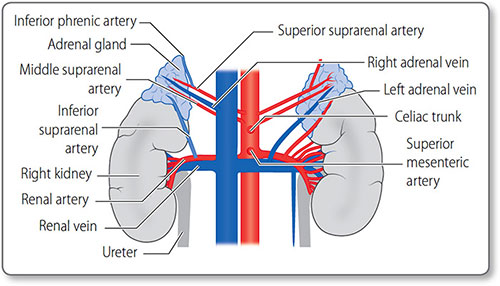

Renal vessels The renal arteries arise as lateral branches from the aorta at the level of the L1 vertebra (Figure 1.16). They are large in caliber – 0.5–1 cm – reflecting the high level of kidney perfusion, about a quarter of total cardiac output. They divide into segmental, lobar, interlobar and arcuate arteries before becoming the afferent arterioles supplying the glomeruli.

Figure 1.16: The arteries and veins of the kidneys and adrenal glands. The major vessels are the inferior vena cava and the abdominal aorta.

The renal veins mirror the arteries along their course.

Adrenal vessels The adrenal glands also have a rich blood supply via their superior, middle and inferior suprarenal arteries. These usually arise from the inferior phrenic artery, aorta and renal arteries, respectively. The right adrenal vein drains into the inferior vena cava, whereas the left drains into the left renal vein.